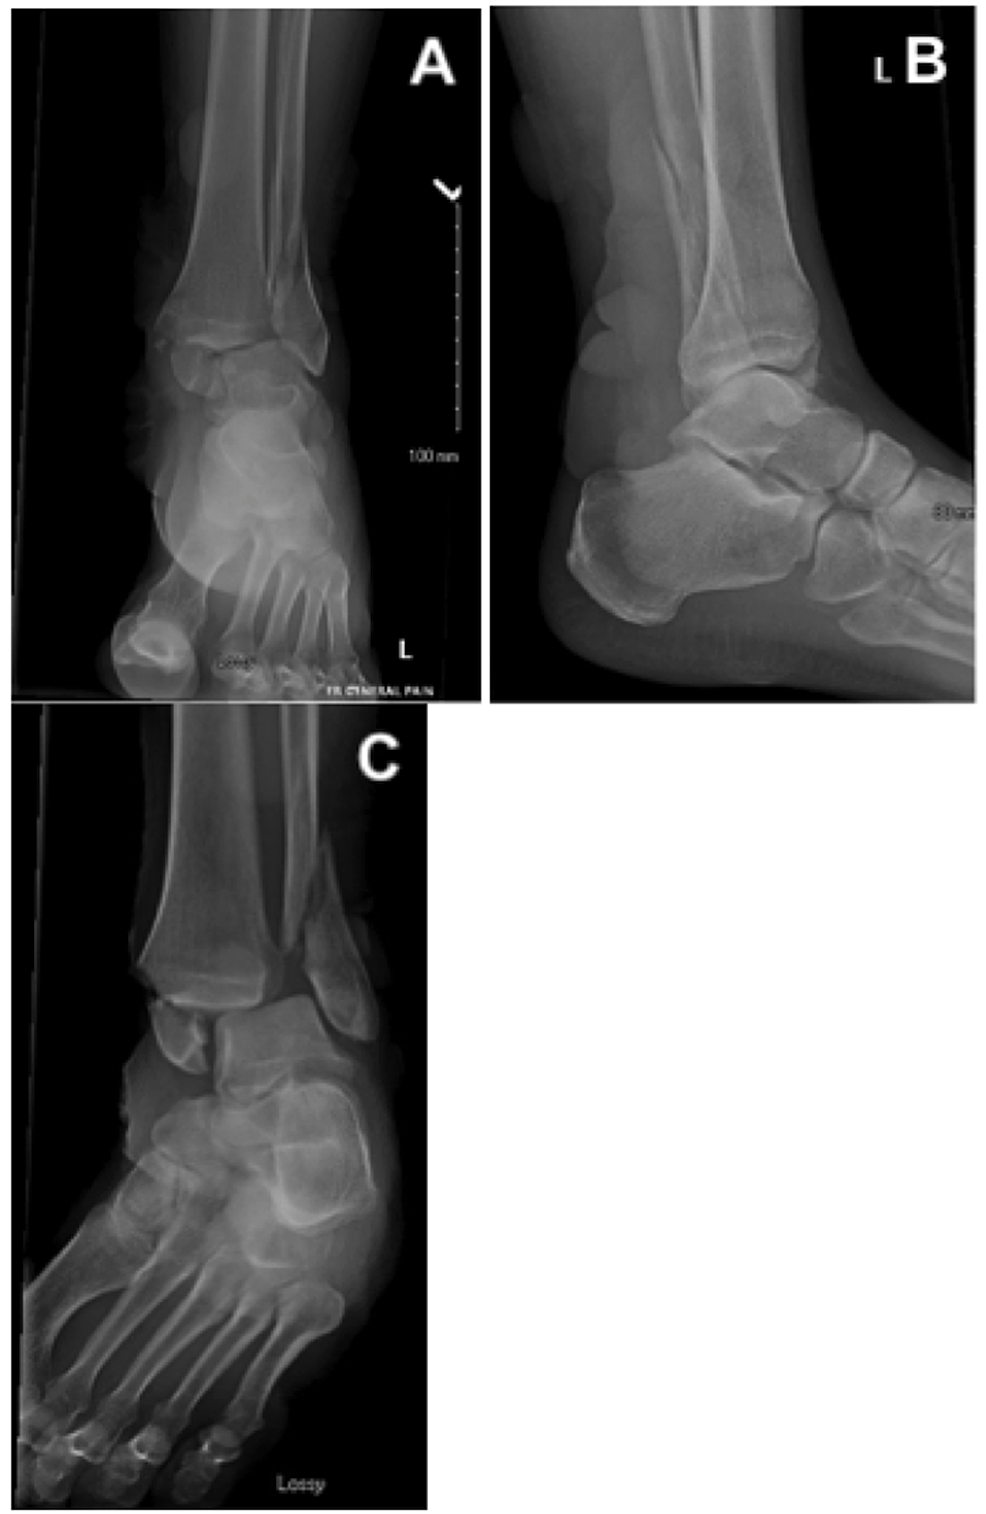

Medial Malleolus FractureCausesSymptomsTreatmentRecovery TimeDiagnosis Fracture Blister Treatment fracture blister complicate approximately 3% of fractures that require hospital treatment. They are more likely to arise over. Treatment with dressings infused with silver has been shown to speed up recovery time from. fracture treatment should ideally take into account two major considerations, the treatment of the bone injury and the. Fracture treatment should ideally take into account. Fracture Blister Treatment.